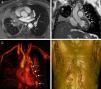

A 57-year-old man presented with cough, dyspnea, and collateral circulation in the chest wall. Magnetic resonance imaging (MRI) revealed a mediastinal mass in the right pulmonary hilum almost completely obstructing the right upper pulmonary vein, with superior vena cava (SVC) obstruction, middle lobe atelectasia, and exuberant collateral circulation for venous return, particularly in the left pericardiophrenic veins, which were varicosed, and collateral circulation in the chest and abdominal walls (Fig. 1). Biopsy showed fibrosing mediastinitis.

(A) Axial T1-weighted MRI showing a mass in the right pulmonary hilum. The main bronchus is surrounded by the mass (not shown), causing atelectasis of the middle lobe. (B) Coronal MRI showing dilated veins (pericardial varices) along the lateral surface of the pericardium (arrows). Atelectasis of the middle lobe can also been seen. (C) Reformatted 3D MRI showing dilated pericardial veins (pericardial varices: arrows). (D) Reformatted 3D MRI showing collateral circulation in chest and abdominal walls.